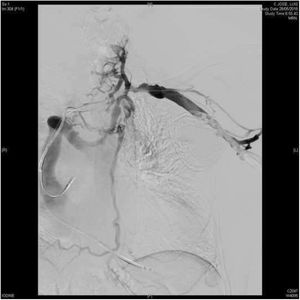

El sistema láser excimer permite la extracción de electrodos de DEIC incluso cuando el sistema venoso está parcial o totalmente ocluido (fig. 4). La complejidad de los pacientes tratados en las series más recientes viene definida tanto por la antigüedad de los electrodos extraídos como por la elevada prevalencia de alteraciones en la permeabilidad del eje venoso del miembro superior con el DEIC4,7,24,25. En nuestra serie, la flebografía preoperatoria mostró, al menos, un grado moderado de estenosis en el eje venoso del DEIC en un 36,2% de los pacientes y una oclusión completa en el 14,9% de los casos7. De hecho, hemos reportado una tasa de repermeabilización venosa tras el uso del láser excimer superior al 80% en trombosis totales7.